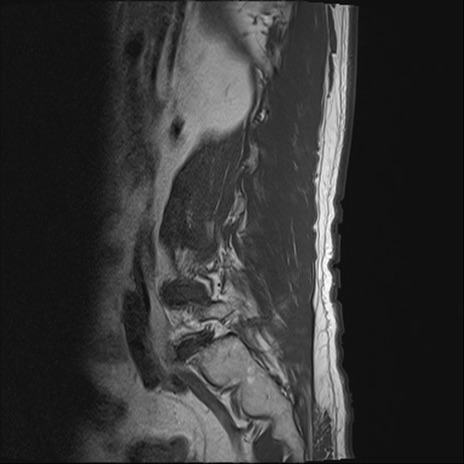

【整形】TIPS症例2 腰椎MRI T1WI(矢状断像)

【症例】70歳代男性

【主訴】左下肢痛

【現病歴】2週間前くらいから腰痛、左下肢痛あり。左臀部から大腿、下腿外側のしびれが常時ある。歩行とともに同部位の痛みあり。

【身体所見】Lasegue70-/60+、Bragard-/±、PTR ±/±、ATR -/-、IP 5/5、TA 5/4、TS 5/5、EHL 右第1足趾なし/3、FHL 5/5、hypersthesia(-)、足背動脈触知良好

異常所見と診断は?